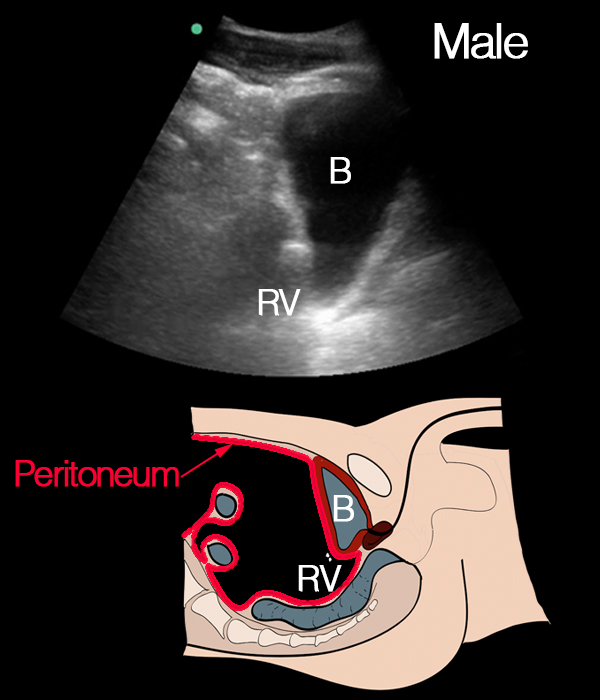

Longitudinal view of the bladder without free fluid in the abdomen: This longitudinal view shows a full bladder on the right side of the image, with no evidence of free fluid in the abdomen. On the left and below the bladder, the normal pattern of intraabdominal contents, including intestines, can be seen, confirming the absence of free fluid in this region. The small round hypoechoic structure seen at the top is content inside a gut.